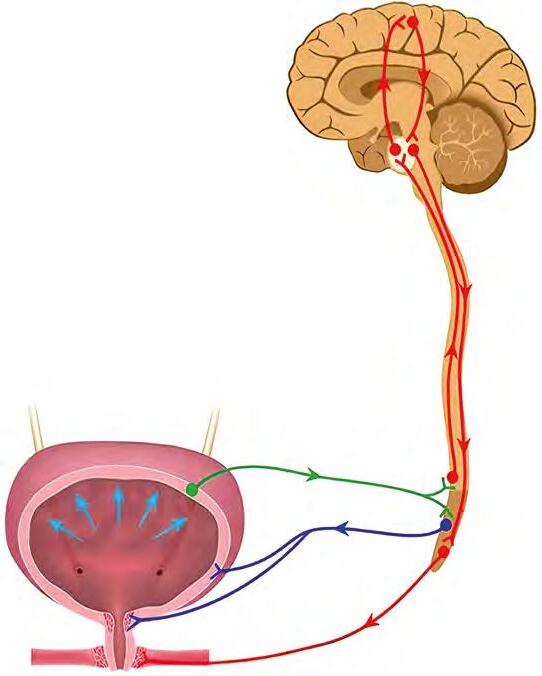

До вісцеральних рефлексів спинного

виділення, дефекації, статеві тощо, які регулюються на рівні крижових сегментів. Вони можуть контролюватися вищими відділами нервової системи.

кишці. Центр

мозку. Під його впливом

сфінктера й посилюється перистальтика кишки.

буває під гальмівним контролем